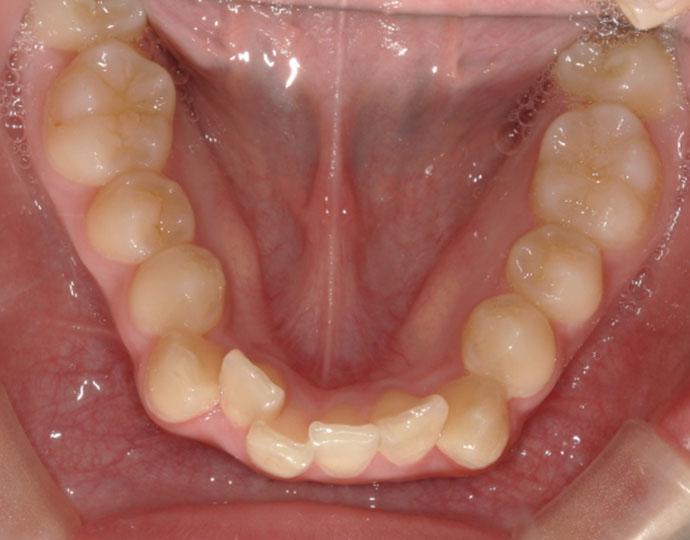

治療前

| 診断 | 叢生歯列不正咬合 |

| 治療方針 | 上下顎左右第一小臼歯の抜歯(計4歯) |